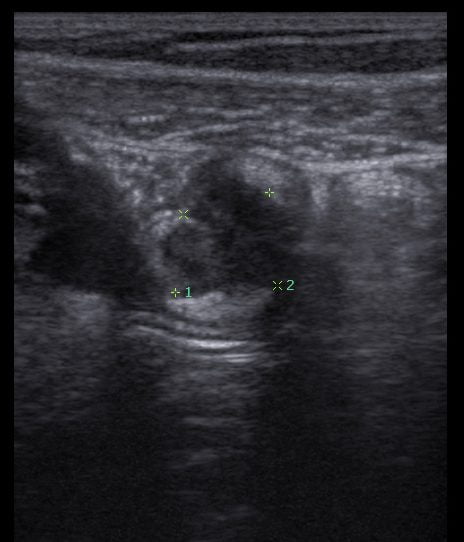

Imagem de ultrassom transvaginal com preparo intestinal, evidenciando endometriose no apêndice.